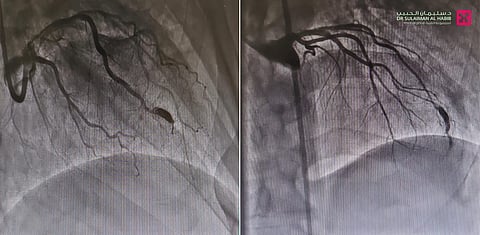

وقال د. فيصل الصميدي استشاري أمراض القلب وقسطرة الشرايين ورئيس الفريق الطبي المعالج، أن المراجع ظل يعاني منذ سنوات من ألم في منتصف الصدر، والإرهاق وحرقة المعدة والغثيان وضيق النفس، ومؤخراً تزايدت حدة هذه الأعراض، وأثرت على نمط حياته اليومية، فراجع المستشفى وأجريت له سلسلة من الفحوصات الطبية، كاختبار الجهد وتخطيط القلب والأشعة الصوتية، وقد أظهرت النتائج وجود انسدادات بالشرايين التاجية للقلب، ومن ثم خضع لقسطرة استكشافية أظهرت بدورها وجود توسع شديد في الشريان التاجي الأمامي، وسبب التوسع نقصاً في التروية في بعض أجزاء القلب، مما أثر على أجزاء معينة من عضلة القلب.

وتابع قائلاً أن الفريق الطبي قام بعد دراسة الحالة، ووضع خطة علاجية متكاملة تناسب حالة المراجع، وأجرى عملية متقدمة بتقنية القسطرة القلبية، تم فيها إزالة الانسدادات عن الشرايين التاجية، كما تم عمل إجراء طبي غير جراحي لسد التوسع الشديد في الشريان التاجي، عن طريق القسطرة التاجية "COILING" بالدخول عبر الشريان الفخذي، وتعمل هذه التقنية على سد التمدد ومنع تدفق الدم إليه، مما يقلل من خطر انفجاره، وهي تتميز بالفعالية العالية، ولا تتطلب شقوق جراحية كبيرة، وتجرى تحت التخدير الموضعي، إضافة إلى أنها أكثر أماناً وأقل مضاعفات مقارنة بالجراحة التقليدية.

وقد تكلل الإجراء ولله الحمد بالنجاح وحقق نتائج ممتازة.